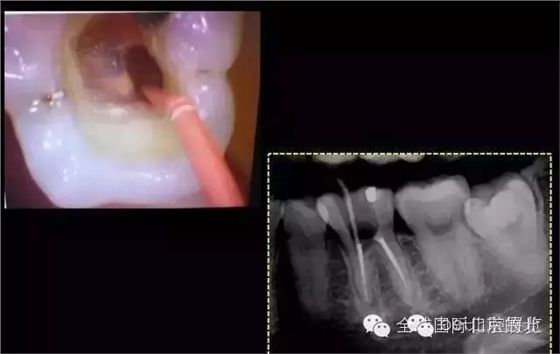

第三次復(fù)查:暫封完好,無明顯叩痛。 去除暫封物繼續(xù)尋找MB,繼續(xù)尋找之前,用樹脂將根充完成的DB,DL根管口封閉,MB的位置暫時(shí)先不封,防止堵塞MB,剛開始還是找不到MB,然后從頰側(cè)的楔狀缺損入手才得以發(fā)現(xiàn)MB的入口,把楔缺擴(kuò)大去腐干凈。

終于找到MB了,然后把根管口MM,ML封閉,S3機(jī)擴(kuò),F(xiàn)1.04錐度牙膠試尖,期盼了好久的柳暗花明終于出現(xiàn)。

終于完成根充

MM,ML其實(shí)融合為一個(gè)根管口的,截面就是三根管的形態(tài),然后做了一個(gè)簡單清晰的三維重建,形態(tài)還是挺不錯(cuò)的 。 一個(gè)月后復(fù)查,如果無明顯反應(yīng)就進(jìn)行及時(shí)的冠修復(fù),做好冠方封閉 以后3-6個(gè)月再做跟蹤回訪